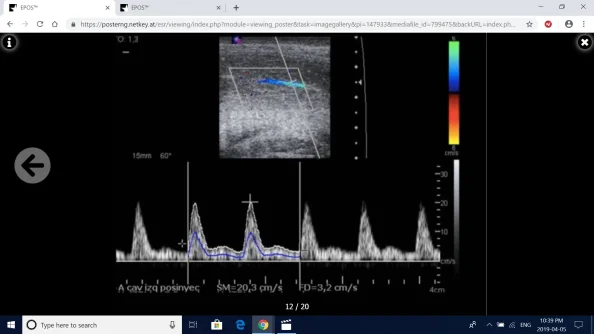

Screenshot (88).webp

Fig. 12: Stimulated CDUS after PGE-1 injection. Arterial Insufficiency. PSV of 20,3 cm/s, EDV of 3,4 cm/s, RI<0,75.

References: Radiology, Hospital Fundación Jiménez Díaz, Hospital Universitario Fundación Jiménez díaz - Madrid/ES